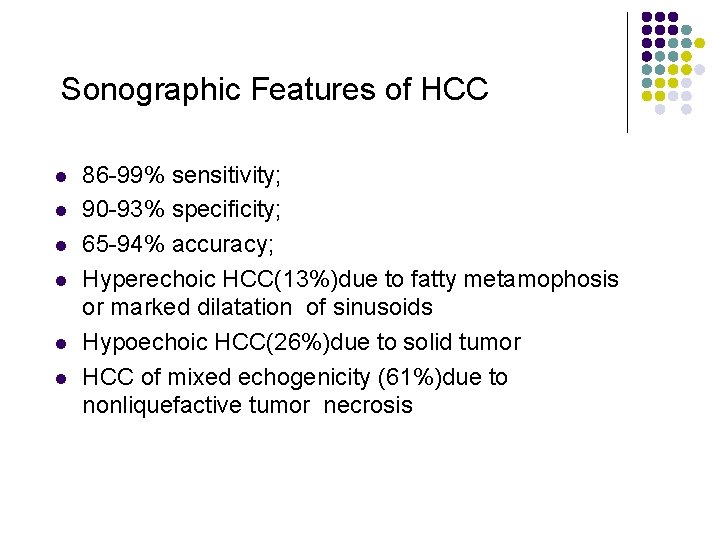

Sonographic Features of HCC l l l 86 -99% sensitivity; 90 -93% specificity; 65 -94% accuracy; Hyperechoic HCC(13%)due to fatty metamophosis or marked dilatation of sinusoids Hypoechoic HCC(26%)due to solid tumor HCC of mixed echogenicity (61%)due to nonliquefactive tumor necrosis